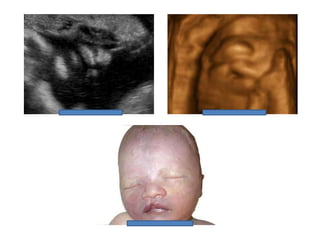

Binder Phenotype

a flat profile and depressed nasal bridge.

Short nose, short columella, flat naso-labial angle and

perialar flattening

Isolated Binder Phenotype transmission would be

autosomal dominant

Binder Phenotype can also be an important sign of

chondrodysplasia punctata (CDDP)